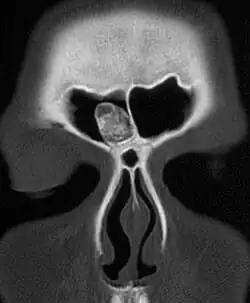

Un ostéome vu au scanner.

Un ostéome est une tumeur bénigne osseuse.

Il est souvent localisé au niveau des sinus paranasaux avec une prévalence de 3 %[1].